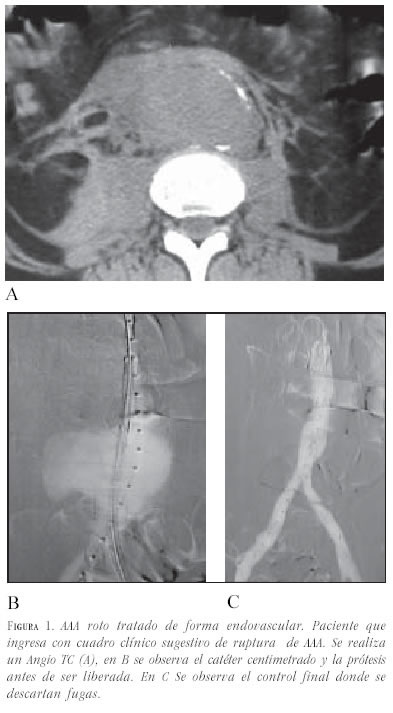

En casos de oclusión completa de un eje ilíaco, se puede intentar su recanalización; cuando ésta resulte infructuosa, se utiliza una endoprótesis monoilíaca y un puente femorofemoral (23).

- Diámetro de las arterias ilíacas: se debe evaluar el diámetro de las arterias ilíacas tanto para el paso del transportador de la endoprótesis, como para calcular el diámetro de la rama que asegure el adecuado sellado en el punto de contacto. El diámetro mínimo para el paso del transportador es de 7,5 mm. En casos de diámetro menor a 7,5 mm, estenosis severa u oclusión, deberán ser tratados previamente con angioplastia. Si la gran cantidad de calcio o el pequeño diámetro en toda su longitud impiden el avanzar el transportador, se puede realizar un by pass temporal a la arteria ilíaca, dejando un extremo libre que permita pasar la endoprótesis. Se describe esta técnica más adelante en este artículo.